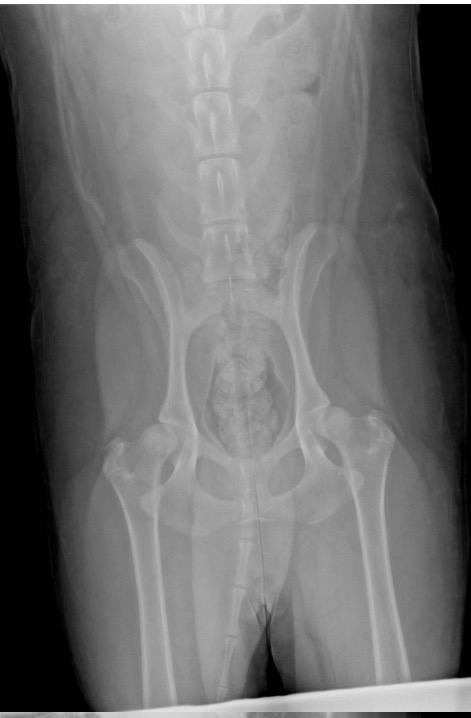

10mth old standard poodle. Already has developed hip dysplasia. Can I sue the breeders? Three vets saying she needs TPO. Breeders gave oral statement that no HD in their line. Should have gotten proffered of the two tests but...... They have a cease and desist order now against me (because I txted them and told them I'd sent the info THEY requested to their vet). Sounds shady. I know one other girl that got a Labradoodle from same sire as mine and vet said 95% will have HD. PLEASE ANYSUGGESTION.